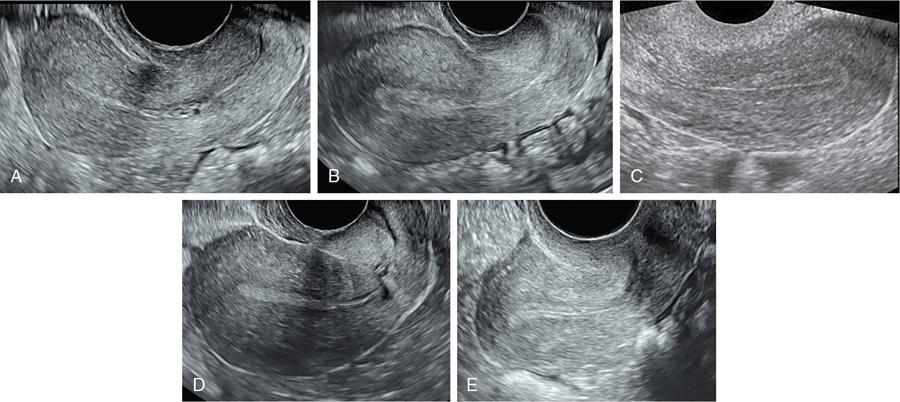

P. Reginald Wesley The imaging appearance of the uterus and ovaries depend on age and sexual maturation of the individual as they are under hormonal influence. Furthermore, the endometrium and ovaries vary their appearance depending on the time of imaging during the menstrual cycle. Fig. 11.3.1 shows the technique of measuring the uterus. Uterine length is more accurately measured with transabdominal ultrasound compared to transvaginal scan where the cervix may not be included within the field of view. Table 11.3.1 shows the normal uterine length and size ratio between the uterus and cervix in various age groups. Optimally assessed by transvaginal ultrasound. It represents the sum of the thickness of the two endometrial layers. To measure the endometrium, first the midline longitudinal image of the uterus is taken. Then place the cursor at the interface between the endometrium and the myometrium at the anterior and posterior walls of the uterus. Fig. 11.3.2 shows the appearance of the endometrium in various stages of menstrual cycle. The measurement is preferably taken at the fundal region with widest endometrium (Fig. 11.3.3). The echogenic line at the centre denotes the interface where the anterior endometrial layer opposes the posterior endometrial layer. The hypoechoic layer peripheral to the endometrium represents the inner layer of myometrium and should not be included while measuring the endometrial thickness. Table 11.3.2 shows the endometrial thickness and appearance in different stages of menstrual cycle. Ideally, transvaginal ultrasound is better because of its higher resolution especially in the assessment of polycystic ovaries. However, transabdominal scan has its use in adolescent girls and virginal women. It is also useful in cases of displaced ovaries. Fig. 11.3.4 shows the technique of measuring the ovarian volume. While measuring the volume in transabdominal scan, urinary bladder should be adequately distended. However, care should be taken not to over distend the bladder as it may compress the ovaries leading to incorrect measurement of the size. Bladder distension is not required for transvaginal ultrasound. Table 11.3.3 shows the appearance and size of ovaries in various age groups. According to the technical recommendation for the assessment of polycystic ovaries as per 2003 Rotterdam PCOS consensus: Time of performing ultrasound: Women who have regular menstrual cycles – early follicular phase between days 3 and 5. Women who are oligomenorrheic or amenorrheic – random or between 3 and 5 days after inducing withdrawal bleeding following progestin administration. Estimation of the number of follicles – done in both longitudinal and anteroposterior planes of the ovaries. The follicles which measure less than 10 mm, their size should be given as the average of the two diameters measured in each plane. Presence of 12 or more follicles in each ovary measuring 2–9 mm in size and/or ovarian volume of more than 10 mL. Ovarian volume is a surrogate measurement for stromal hypertrophy. The presence of a single polycystic ovary is sufficient for the diagnosis of polycystic ovary syndrome (PCOS). Measurement of the number of follicles (antral follicle count) should be done in longitudinal plane. Measurement of the size and distribution of the antral follicles should be done in orthogonal plane. Average of two orthogonal measurements is used for antral follicle diameter. In PCOS, there is ovarian androgenic dysfunction, which leads to stromal hypertrophy. This is called hyperthecosis where there is enlarged ovaries with increased stromal thickness and echogenicity without mature follicles. This is indicated by the stromal area. To measure the areas, first the stroma is identified which is represented by the central echogenic area of the ovary. Using the callipers, this central area is measured along with its outer margin. Then the total area of the ovary is measured by placing the callipers along with the outer margin of the ovary (Fig. 11.3.5).

How to measure the endometrium?